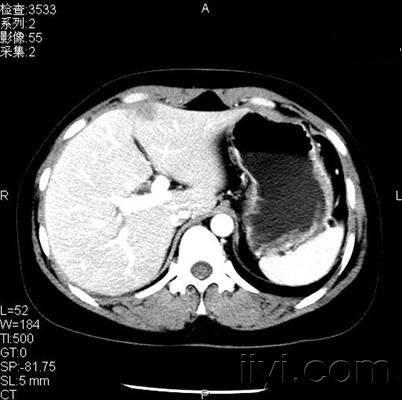

患者,女性,体检发现肝左叶低密度病变2天

平衡期